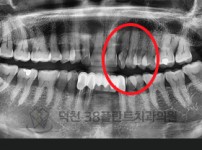

치료전후